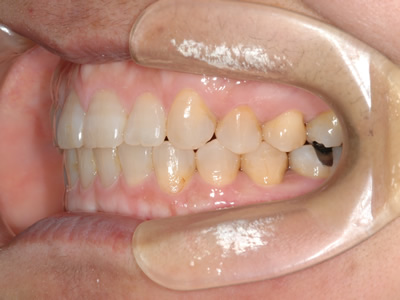

上顎前歯部のガタガタを気にして来院されました。上顎の左右第一小臼歯 (4番目の歯) を抜歯し、マルチブラケット装置で治療しました。治療期間は2年3か月でした。

初診時

終了時